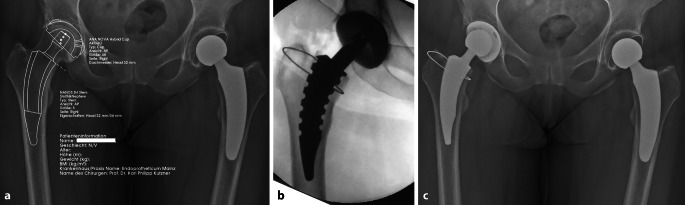

Short stems in total hip arthroplasty are increasingly being established and offer several advantages in terms of minimal invasiveness and bone preservation compared to standard implants. The rounded design and shorter stem length facilitate better adaptation to natural anatomy, at the same time also posing specific risks and complications. When transitioning to short stems, a learning curve must be considered. Careful patient selection and preoperative planning are crucial, and intraoperative imaging is recommended. The most common implant-specific complications include insufficient osseointegration, leading to subsidence and aseptic loosening, as well as periprosthetic fractures. The risk instability and dislocations as well as periprosthetic infections can potentially be reduced with short stems. This article discusses the frequency, causes, and treatment options for these types of complications and highlights current evidence-based treatment approaches.